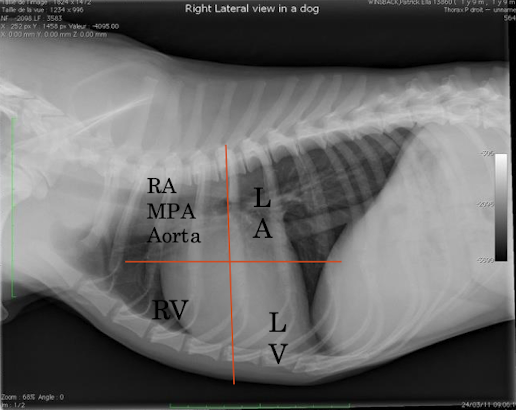

What are seen in each quadrant?

Label